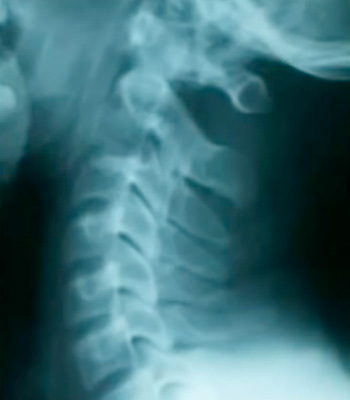

正常な頚椎のカーブ

ストレートネックは長期の首に負担をかける姿勢が続くことでじわじわと首のカーブが無くなりそして、首だけでなく背中や腰、骨盤・股関節に膝などの関節の位置がおかしくなり身体のあちこちで症状を引き起すきっかけになることも多くあります。